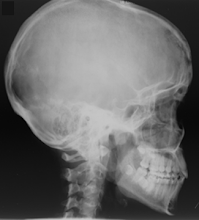

Sweat is beading and rolling from my forehead down underneath my mask and dripping from my chin onto the control panel of the c-arm fluoroscopic unit I’m currently using to image an ankle undergoing hardware implantation. I cringe as my lead thyroid shield comes undone and falls to the filthy OR floor, but instead of going without it I quickly wipe of the grime and reattach the shield around my neck. There is a moderate amount of stress in the OR, especially as a student who has never utilized this technology before, especially while wearing the ceil blue full-body jumpsuit, hairnet and surgical mask… Especially as a renowned orthopedic surgeon is testing your competence and critical thinking skills… I’ve seen him rip into other techs in previous weeks, and I’m praying that I get through this without any obvious mistakes. I’ve noticed that the OR can be a brutal environment for students and seasoned techs alike, though my goal is to have an excellent first experience manning the controls.